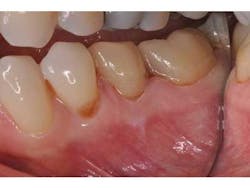

The exposed dentin and enamel surfaces are first treated with a chlorhexidine antibacterial slurry (Conspesis Scrub, Ultradent) to remove residual provisional cement and lower bacterial loads (Fig. 6). This step has been shown to increase the bond strength of adhesive resin cements. (8) After wash and removal of the hemostatic and antibacterial solutions, the area was able to be isolated with dry cotton rolls. If isolation is difficult, the clinician may choose to place a rubber dam. The decontaminated and isolated tooth surfaces are treated with a self-etch primer (Multilink Primer A and B, Ivoclar) (Fig. 7). After drying and light-curing the teeth, the restorations are filled with a dual-cure adhesive resin cement (Multilink Automix, Ivoclar) and seated. Excess cement is removed and the final restorations may be polished (Fig. 8).